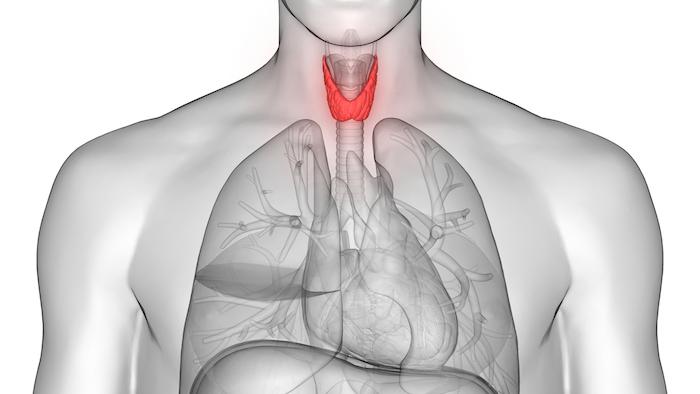

Bien qu’elle ne pèse que 30 grammes en moyenne, la thyroïde est une petite glande endocrine en forme de papillon située à la base du cou qui régule nos systèmes hormonaux, notamment par la sécrétion de thyroxine (T4) et de tri-iodothyronine (T3). Schématiquement, la première hormone a pour rôle d’accélérer toutes les réactions chimiques de notre corps. La seconde participe à la régulation du calcium dans notre sang. Ces hormones sont transportées dans le sang et diffusent dans toutes les parties du corps.

Globalement, la thyroïde drive notre métabolisme en fournissant de l'énergie à notre organisme et en régulant le fonctionnement des organes. De fait, elle agit sur la température corporelle, le système nerveux, le tube digestif, l’appareil génital, les cheveux, la peau, etc... et donc, sur le bien-être général d'un individu.

Comme le détaille l'Institut du Cancer, chez l'enfant, les hormones thyroïdiennes "participent à la croissance et au développement du corps par leur action sur le système nerveux et le squelette. A l'âge adulte, elles contribuent au fonctionnement du système nerveux et à l'entretien des os". Lorsqu'elles sont produites en quantité excessive, on parle d'hyperthyroïdie. A l'inverse, lorsqu'elles sont sécrétées en faible quantité, on parle d'hypothyroïdie. Dans les deux cas, les fonctions du corps sont perturbées.

Photo : illustration d'une thyroïde saine et d'un goitre (Crédit : Lars Neumann/iStock)